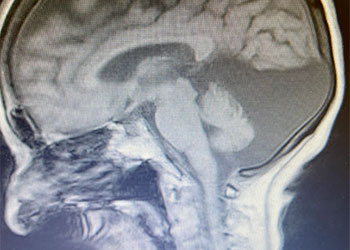

The patient was taken to the angio-suite where an angiogram confirmed a high flow, high pressure AVM fed primarily by the posterior cerebral artery with a small collateral from the middle cerebral artery (Fig 2 and 3). The AVM drained into a tortuous, partially occluded and stenotic single draining vein.

Fig 2. AP view, mid-arterial phase of a right internal carotid artery (ICA) injection. The large tortuous draining vein (yellow star) with the suggestion of clot (dotted circle) can be seen. AVM nidus (red arrow), MCA (middle cerebral artery, ACA (anterior cerebral artery).

Fig 3. Lateral view, late-arterial phase of a right internal carotid artery (ICA) injection. Filling of the AMV (red arrow) by the fetal posterior cerebral artery (PCA) and small middle cerebral artery feeder (blue arrow). The large tortuous draining vein (yellow star) with venous stenosis and the suggestion of clot (dotted circle) can be seen.